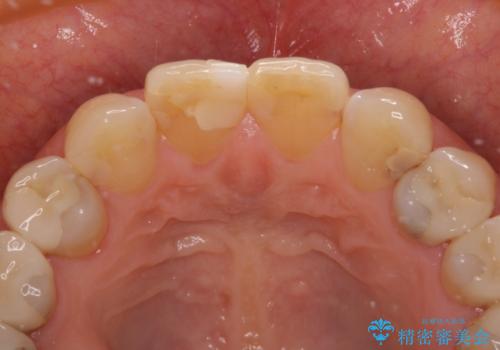

- 上顎2前歯の色を気にして来院された患者様です。

2本ともに虫歯治療による充填材の変色などによりつぎはぎのような前歯となっていたため、オールセラミッククラウンにて補綴治療を行うこととしました。